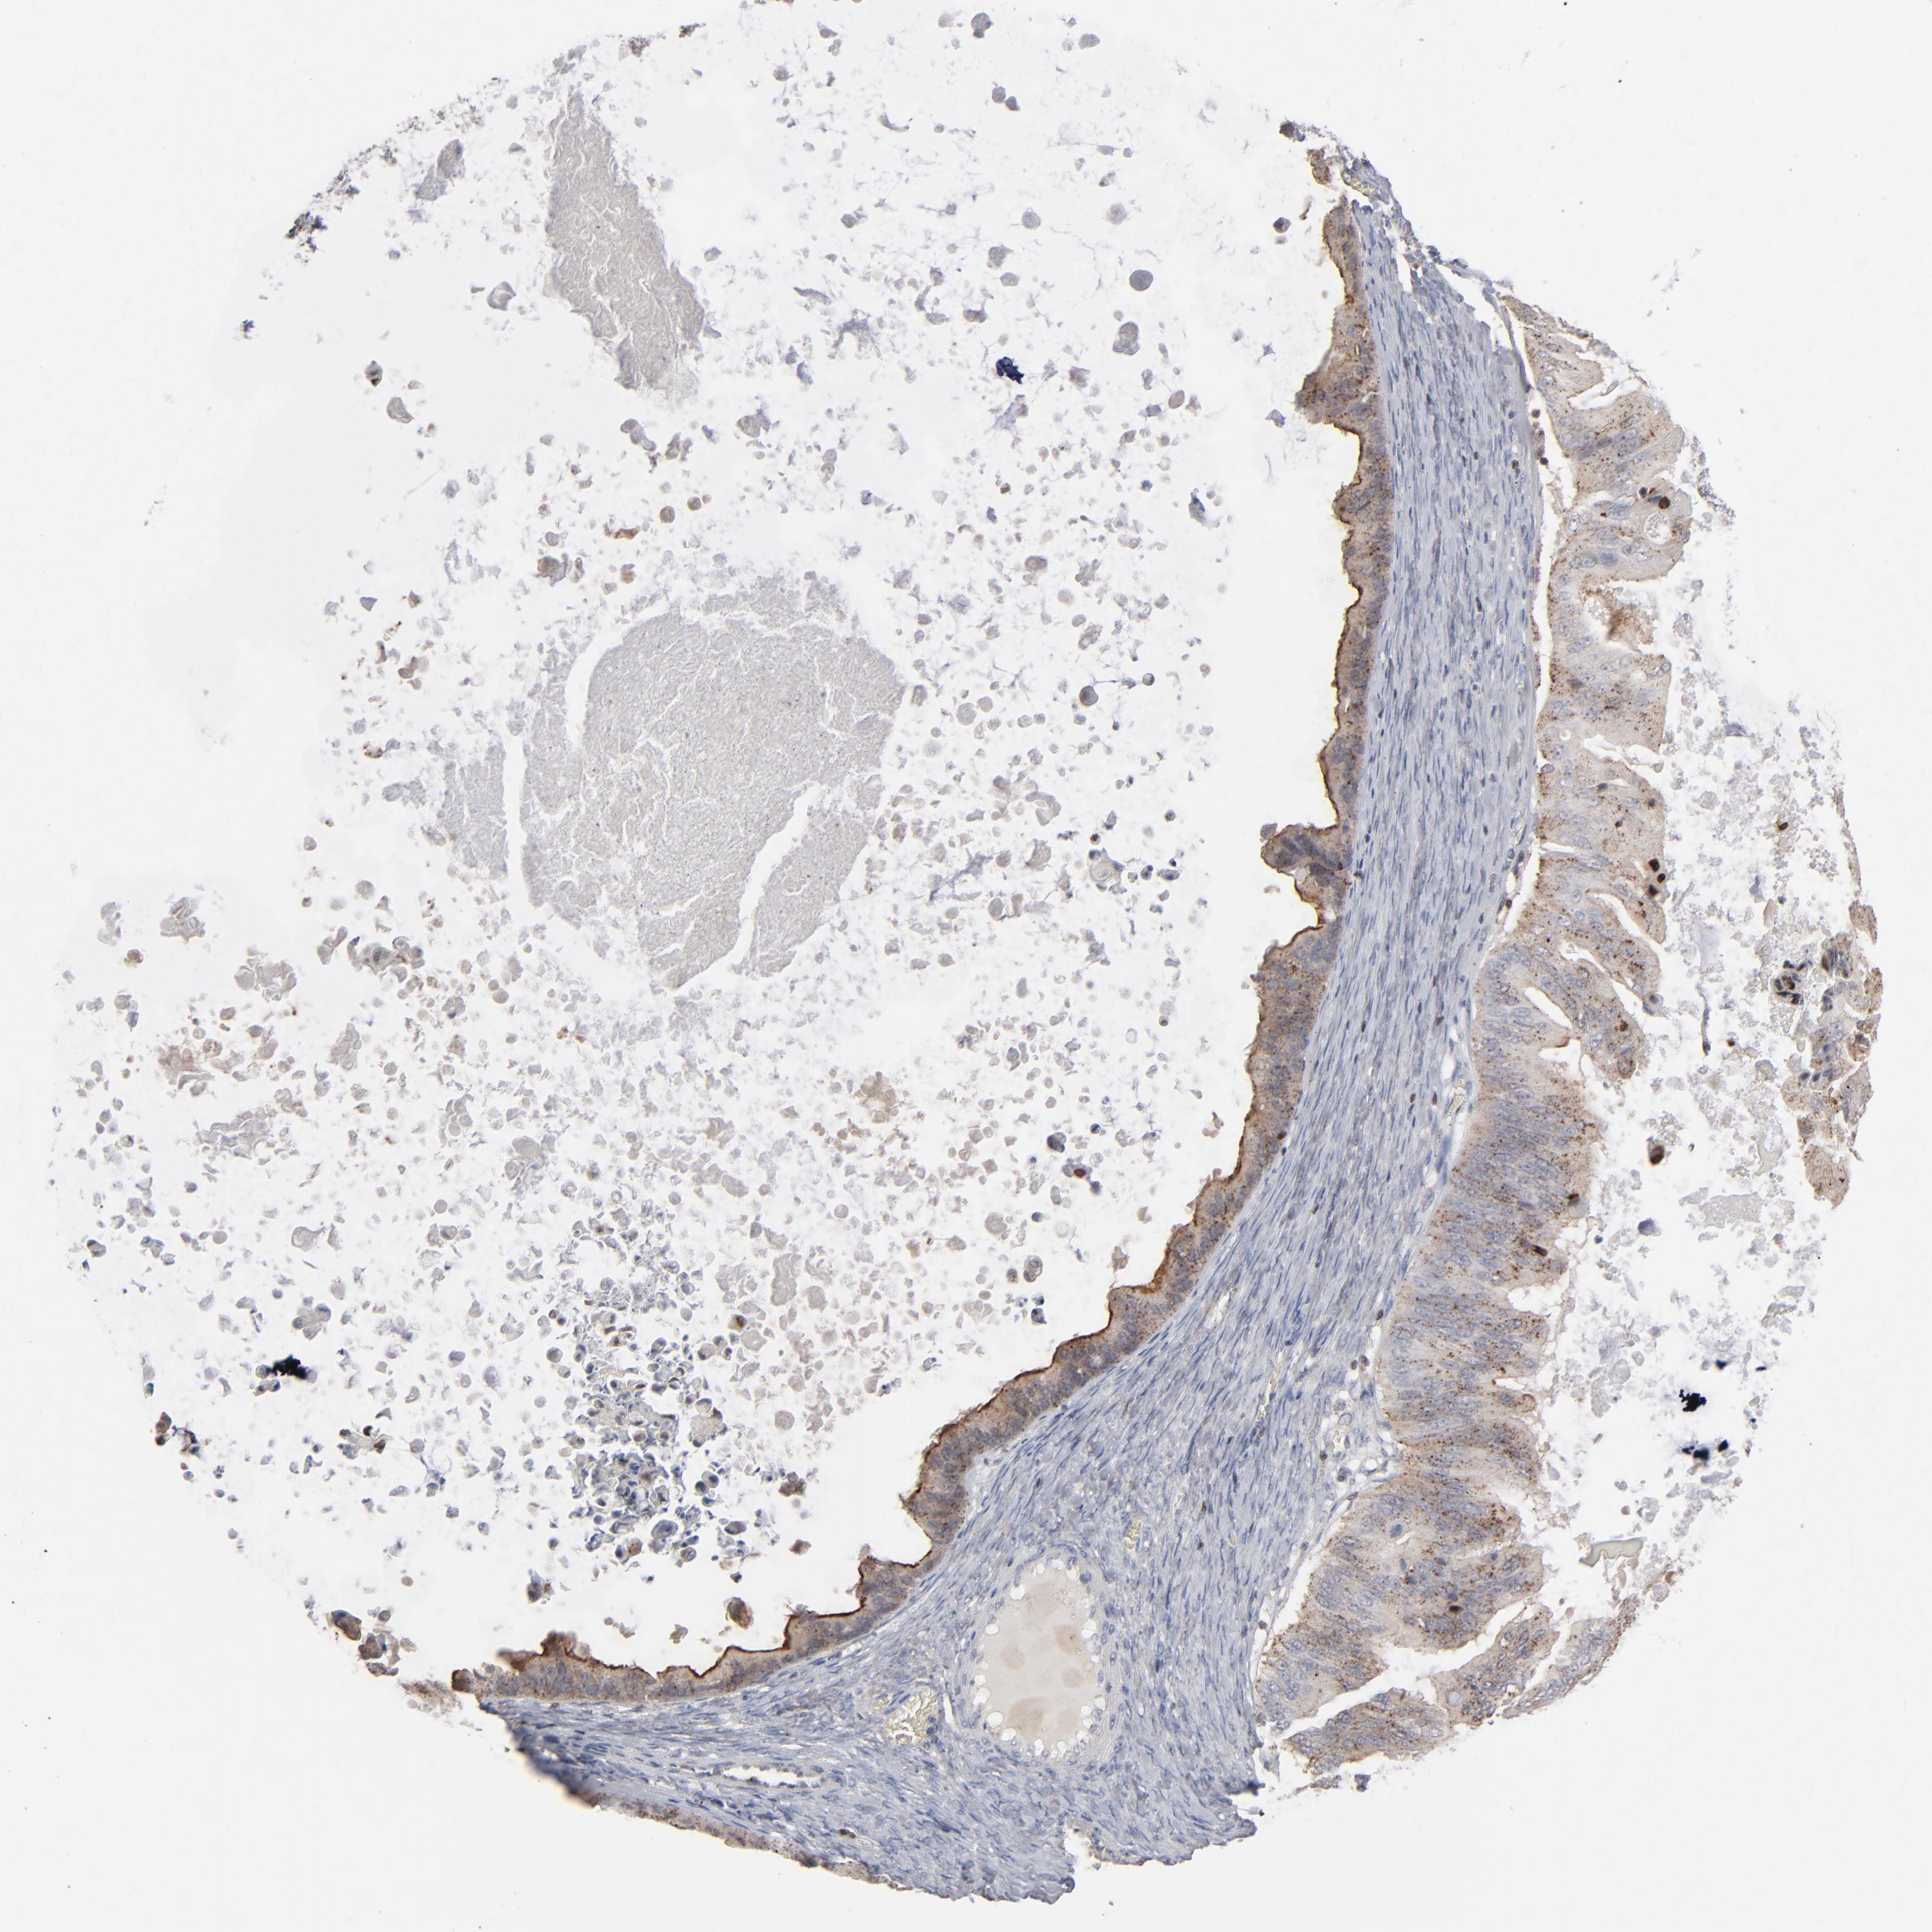

OVARIAN CANCER - Protein expressioni

A mouse-over function shows sample information and annotation data. Click on an image to view it in a full screen mode. Samples can be filtered based on level of antibody staining by selecting one or several of the following categories: high, medium, low and not detected. The assay and annotation is described here.

Note that samples used for immunohistochemistry by the Human Protein Atlas do not correspond to samples in the TCGA dataset.

Antibody stainingi

Antibody staining in the annotated cell types in the current human tissue is reported as not detected, low, medium, or high, based on conventional immunohistochemistry profiling in selected tissues. This score is based on the combination of the staining intensity and fraction of stained cells.

Each image is clickable and will lead to virtual microscopy that enables deeper exploration of all samples and also displays staining intensity scores, fraction scores and subcellular localization as well as patient and tissue information for each sample.

Antibody HPA001860

Antibody CAB013108

Staining

High

Medium

Low

Not detected

Intensity

Strong

Moderate

Weak

Negative

Quantity

>75%

75%-25%

<25%

None

Location

Nuclear

Cytoplasmic/membranous

Cytoplasmic/membranous,nuclear

Cystadenocarcinoma, serous, NOS

Cystadenocarcinoma, mucinous, NOS

Carcinoma, endometroid

Carcinoma, NOS